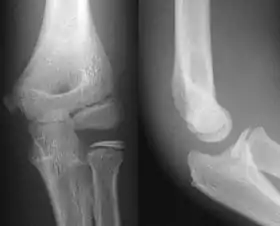

- Elbow - AP and Lateral. Radial head projections available on request

Lateral projection

Anteroposterior projection

Left elbow by 30 degrees internal oblique projection

Left elbow by 30 degrees external oblique projection